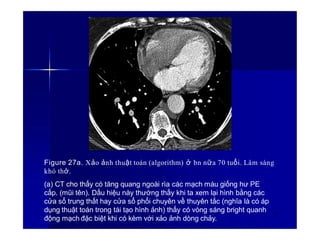

Figure 27a. Xảo ảnh thuật toán (algorithm) ở bn nữa 70 tuổi. Lâm sàng

khó thở.

(a) CT cho thấy có tăng quang ngoài rìa các mạch máu giống hư PE

cấp. (mũi tên). Dấu hiệu này thường thấy khi ta xem lại hình bằng các

cửa sổ trung thất hay cửa sổ phổi chuyên về thuyên tắc (nghĩa là có áp

dụng thuật toán trong tái tạo hình ảnh) thấy có vòng sáng bright quanh

động mạch đặc biệt khi có kèm với xảo ảnh dòng chảy.